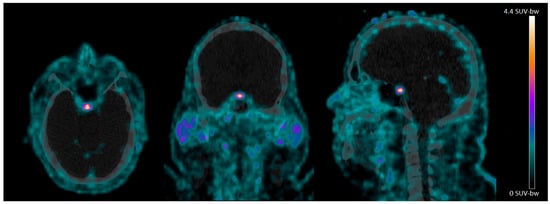

In the CNS, we observed clear 68Ga-NODAGA-exendin-4 uptake in the pituitary area (Figure 1), which was variable between subjects, with a mean SUVmean of 1.7 ± 0.57 (range: 0.88–2.7) and mean SUVmax of 4.3 ± 3.3 (range: 1.4–9.1). However, no 68Ga-NODAGA-exendin-4 uptake was visible in other parts of the brain (mean SUVmean: 0.0010 ± 0.0066 (range: 0.0001–0.21) and SUVmax of 0.17 ± 0.095 (range: 0.013–0.32)) (Table 2).

In this study, we show that there is no significant uptake of 68Ga-NODAGA-exendin-4 in the brain (parts inside the blood–brain barrier; BBB) of subjects with obesity, although there is clear uptake in the pituitary. We also reproduce the accumulation of 68Ga-NODAGA-exendin-4 PET in the pancreas [31].

4.3. No Significant Uptake of 68Ga-NODAGA-Exendin-4 in the Brain

In sum, we only observed uptake in the brain of 68Ga-NODAGA-exendin-4 in the pituitary area of subjects with obesity and it is becoming more likely that (part) of the mechanism of actions of GLP-1 receptor agonists and PET tracers on brain functions might be due to (slow) uptake by tanycytes, located in the median eminence/basal hypothalamus. To shed more light on this topic, it may be relevant to determine whether 68Ga-NODAGA-exendin-4 binds in-vivo in humans only in the pituitary, or also in the median eminence/basal hypothalamus. Additionally, it still cannot be excluded that the central effects of GLP-1 analogues are (partly) induced via peripheral mechanisms and/or by direct uptake via the pituitary/basal hypothalamus.

In conclusion, we have shown that in subjects with obesity there is no significant uptake of 68Ga-NODAGA-exendin-4 in the parts of the brain located within the BBB. Therefore, 68Ga-NODAGA-exendin-4 PET cannot be used to analyze GLP-1 receptors in the brain of obese subjects. However, there is clear uptake of the tracer in the pituitary, which offers the unique opportunity to evaluate the role of GLP-1 receptor expression in the pituitary in health and disease.